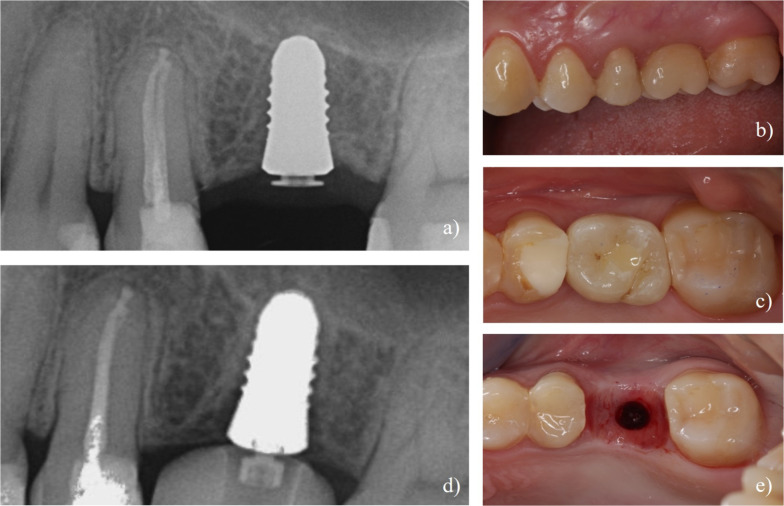

Methods: Twenty-four patients received single two-piece zirconia implants (CERALOG® Hexalobe) in healed sites. After a 6-month healing period, implants received provisional screw-retained crowns on PEKK temporary abutments, followed by definitive lithium disilicate crowns (IPS e.max Press) on PEKK abutments. Clinical and radiographic examinations were performed at implant placement, re-entry, definitive loading, and 12-month follow-up, along with patient-reported outcome measures.

Results: The implant survival rate at 12 months was 60.9%. Nine implants were lost: two due to lack of osseointegration at re-entry, four due to mobility after loading, and three due to fractures in the coronal third after loading. Surviving implants showed stable soft tissue parameters with mean probing pocket depths of 2.7 ± 0.7 mm at 12 months. The mean distance from implant shoulder to first bone contact decreased from 1.9 ± 0.6 mm at loading to 1.4 ± 0.6 mm at 12 months. Patients with surviving implants reported high satisfaction scores (4.8 ± 0.4) for function and aesthetics.